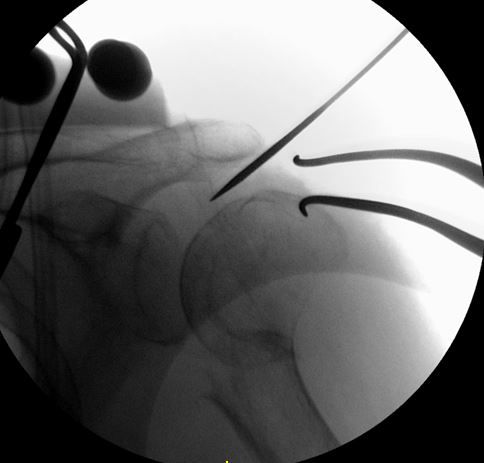

単純X線像上、上腕骨頭が腱板に牽引されて骨幹部と全く連続性がありませんでした。

2 part骨折(外科頚骨折)の場合は、私は手技が簡単なので髄内釘を選択しています。しかし髄内釘の問題点として、エントリーポイントが外側の大結節寄りになりがちなことです。

髄内釘のエントリーポイントを至適にするためには、転位した上腕骨頭を整復する必要があります。私は2.4 K-wireを肩峰外側から上腕骨頭に2本刺入して、これをjoy-stickにして整復します。

2本のK-wireをjoy-stickにして思いっきり整復します。上腕骨頭を内転位に保ちながら、上腕骨頭の頂点からガイドワイヤーを刺入します。

K-wireで上腕骨頭を内転位に整復位を保っておかないと腱板に牽引されて外転転位してしまい、髄内釘のエントリーポイントがかなり大結節寄りになってしまいます。

髄内釘のエントリーポイントが大結節寄りになりすぎると、ネイル挿入時に骨折を併発したり、髄内釘の固定力が落ちるので注意が必要です。この手術で一番重要なポイントだと思います。